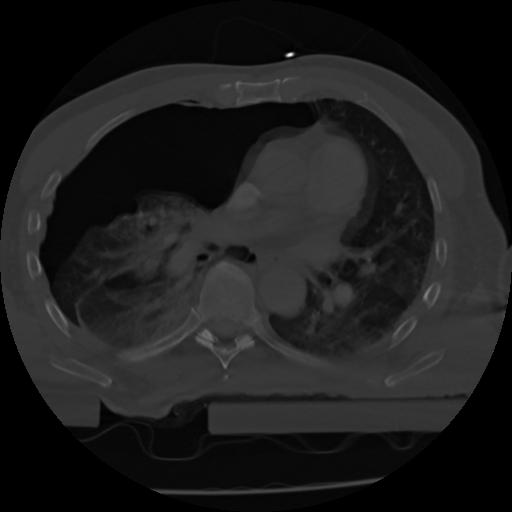

21 ANGIO,CE,Axial,3.0,ANGIO,,